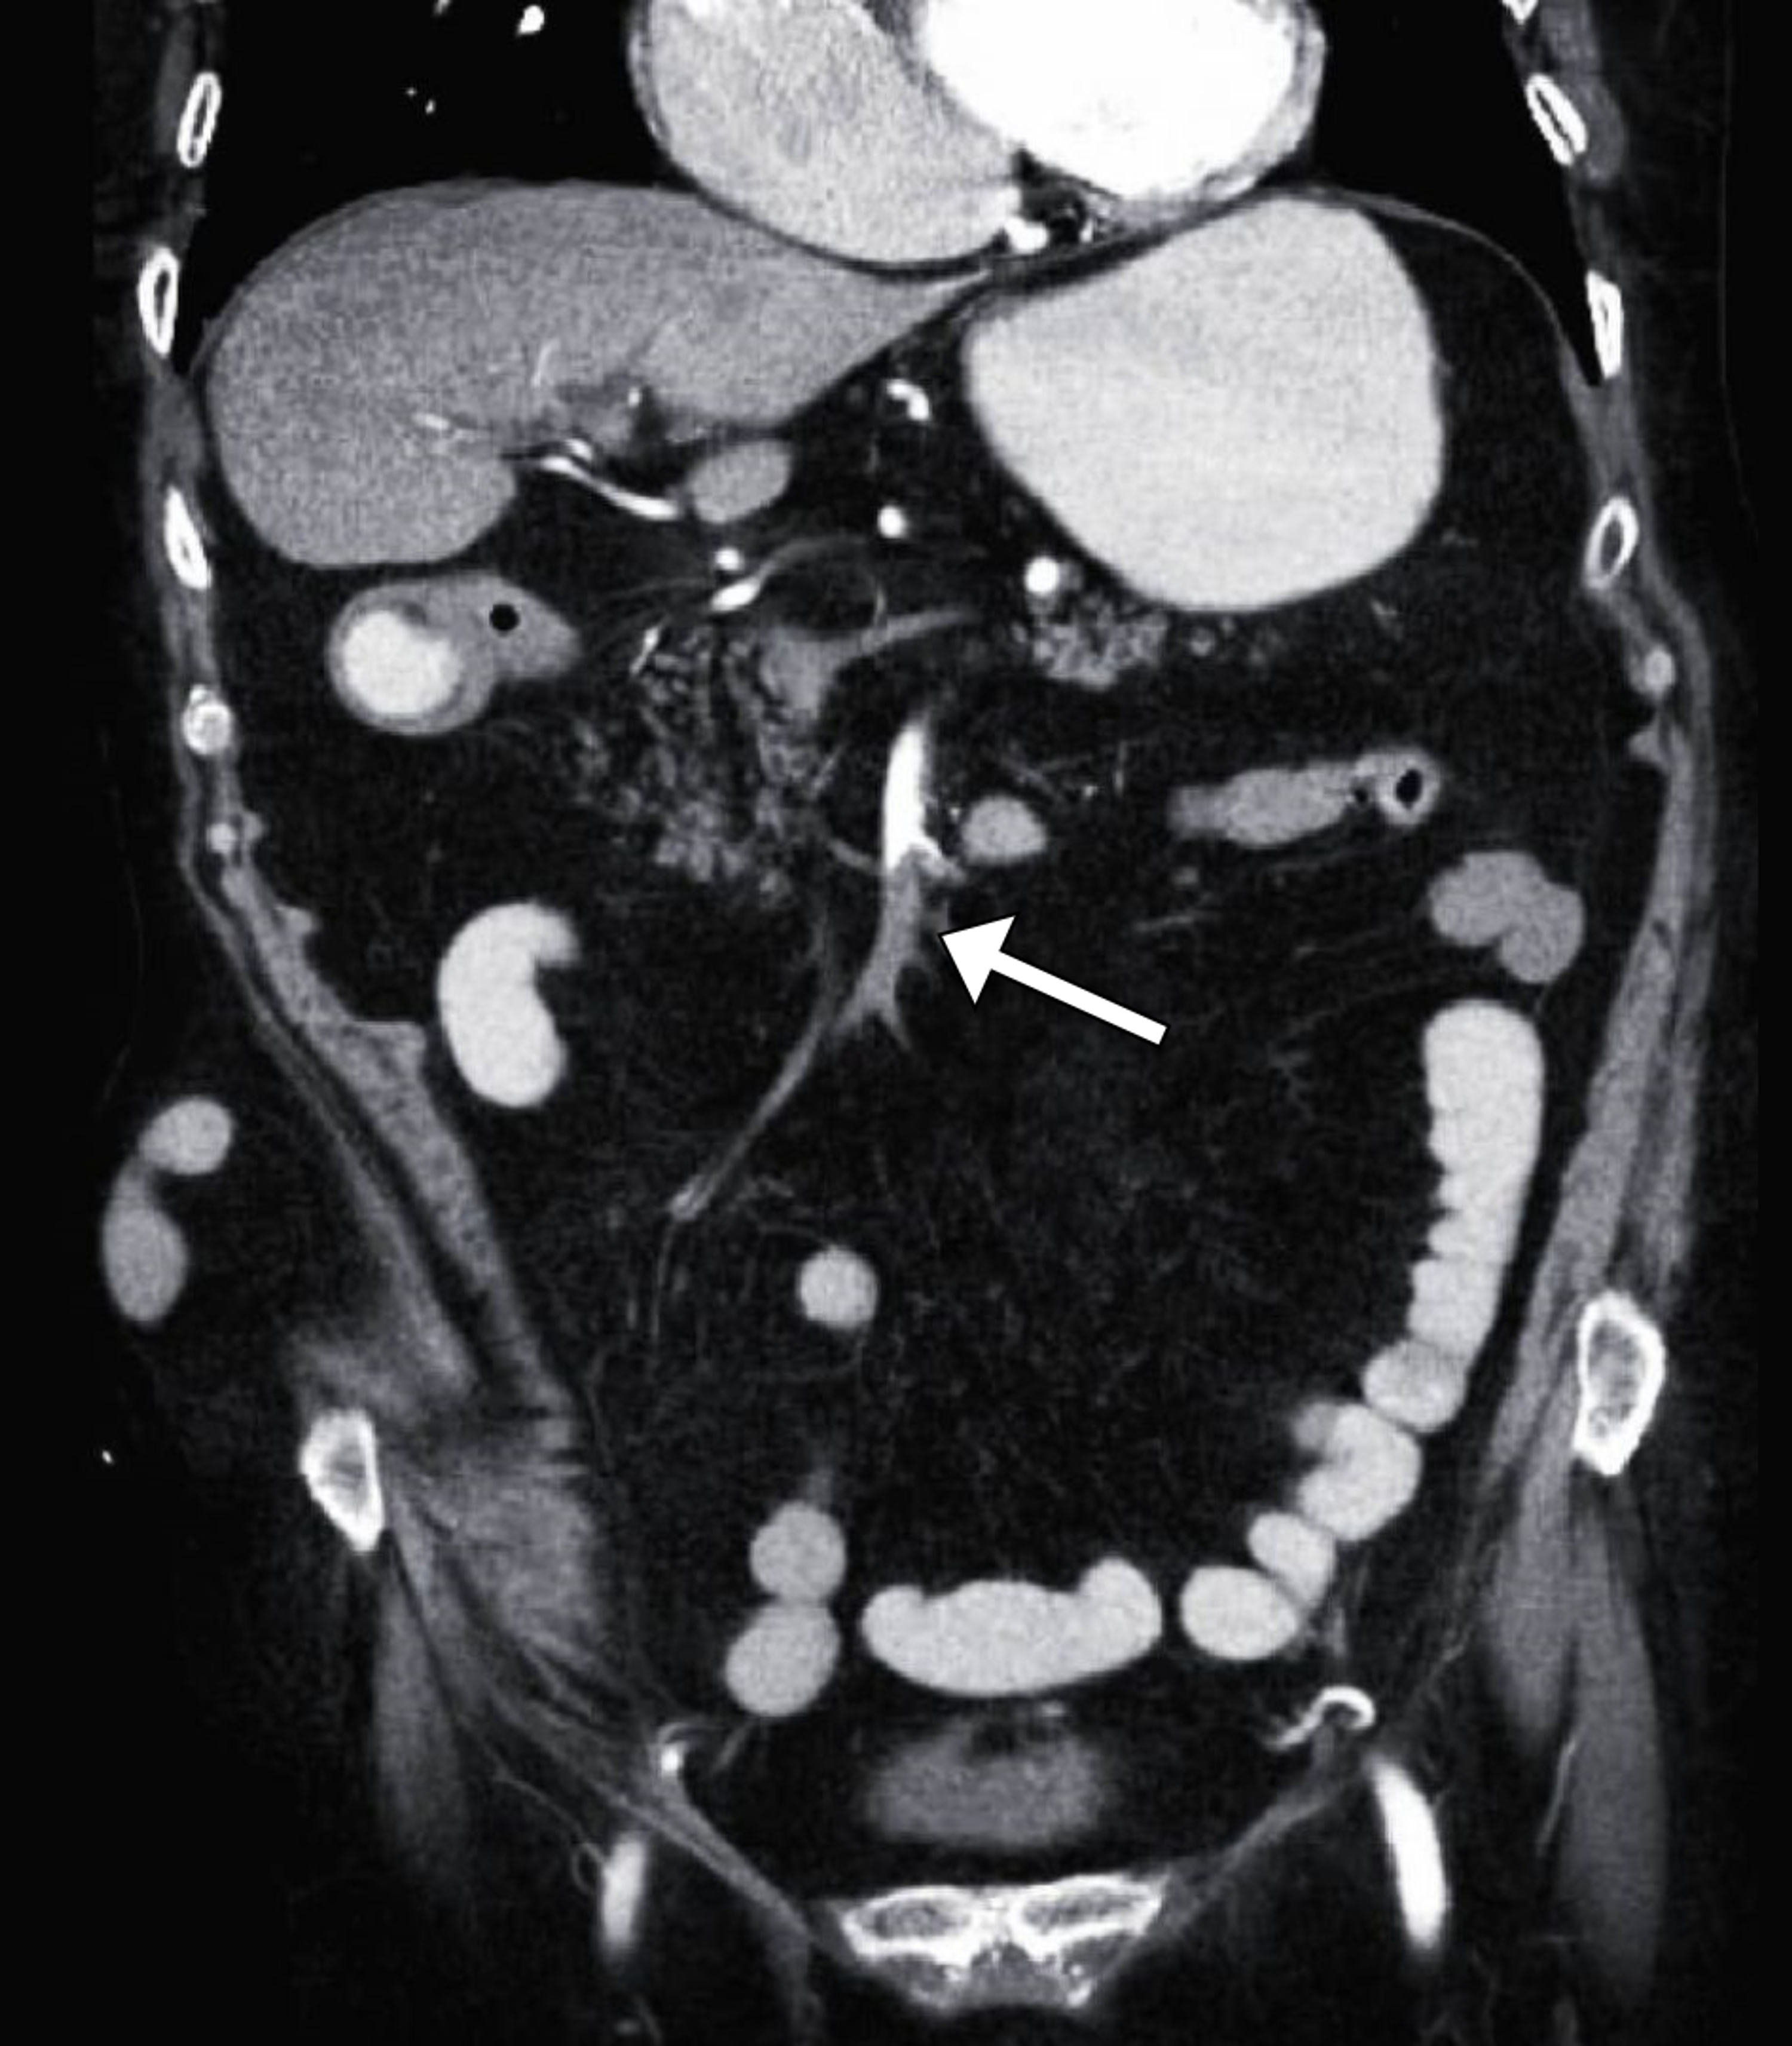

Superior mesenteric artery thrombosis with jejunal ischemia. CASE REPORT A 55-year old man presented to the emergency department with nausea generalized abdominal pain and diarrhea. This condition does not only increase the overall risk for thromboembolism but may also lead to mesenteric ischemia and acute mesenteric artery occlusion diseases associated with high morbidity and mortality. The remainder of the large and small bowel are normal. Rarely the superior mesenteric artery presses against a renal vein or the duodenum causing potentially life-threatening problems.

No evidence of free fluid. In this article we shall look the anatomy of the superior mesenteric artery its anatomical. The bowel was dilated with mural thickening and with some gas in the bowel wall. Thrombus in the proximal superior mesenteric artery. It is a severe and potentially fatal illness typically of the superior mesenteric artery SMA which provides the primary arterial supply to the small intestine and ascending colon1 The occlusion may occur due to in-situ thrombosis of the.

The superior mesenteric artery SMA is a major artery of the abdomen. Mesenteric artery thrombosis MAT is a condition involving occlusion of the arterial vascular supply of the intestinal system. Mesenteric venous thrombosis can decrease the supply of blood to the tissues and cells of your digestive system. This disruption leads to malperfusion of the involved end organ leading to ischemia and ultimately infarction. Thrombus was seen in the superior mesenteric artery and renal vessels and infarction was noted in the kidneys.